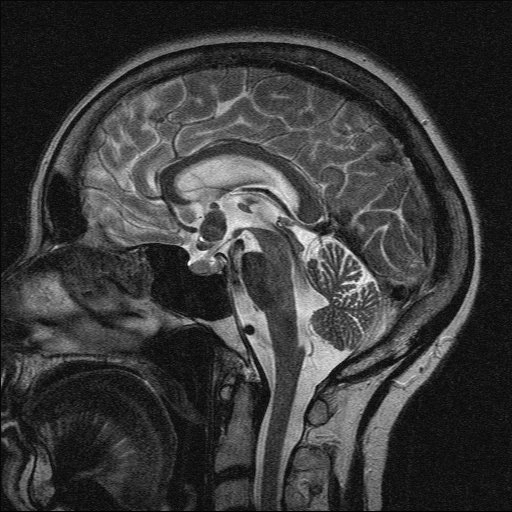

Di căn nhu mô não (Parenchymal metastases)